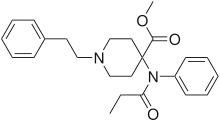

Anilidopiperidines

- 3-Allylfentanyl

- 3-Methylfentanyl

- 3-Methylthiofentanyl

- 4-Phenylfentanyl

- Alfentanil

- α-Methylacetylfentanyl

- α-Methylfentanyl

- α-Methylthiofentanyl

- Benzylfentanyl

- β-hydroxyfentanyl

- β-hydroxythiofentanyl

- β-Methylfentanyl

- Brifentanil

- Butyrfentanyl

- Carfentanil

- Fentanyl

- Lofentanil

- N-Methylcarfentanil

- Mirfentanil

- Ocfentanil

- Ohmefentanyl

- Parafluorofentanyl

- Phenaridine

- R-30490

- Remifentanil

- Sufentanil

- Thenylfentanyl

- Thiofentanyl

- Trefentanil

Structures